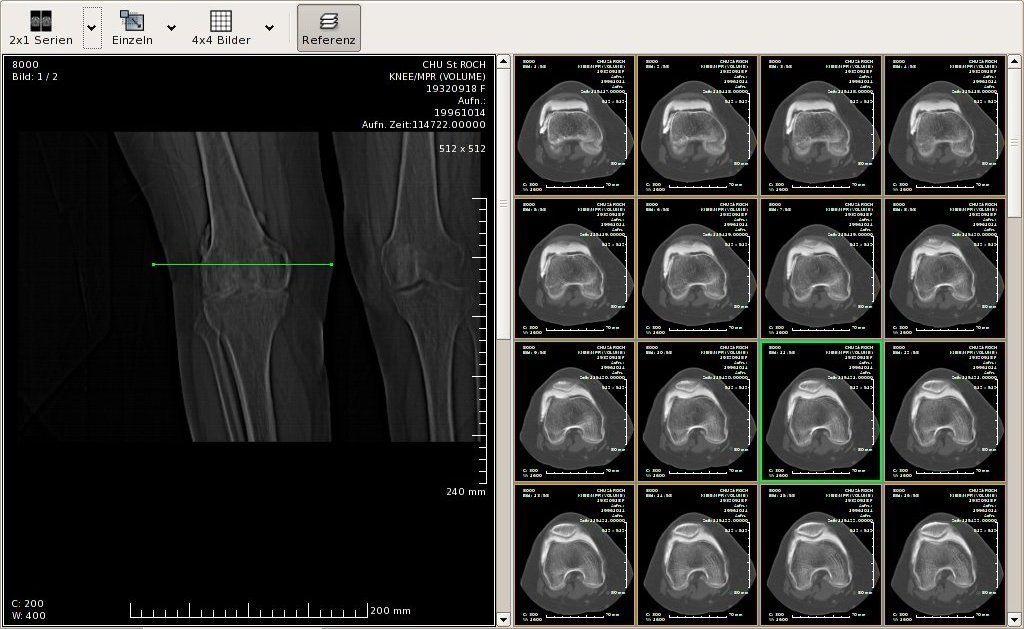

Лазерная камера для печати медицинских изображений на пленке стандарт dicom